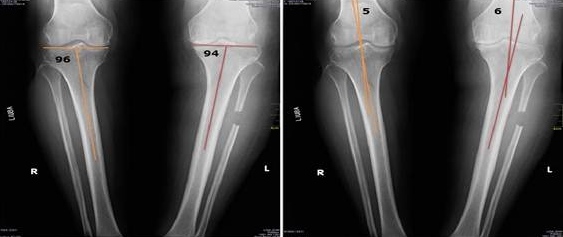

Antes

Después